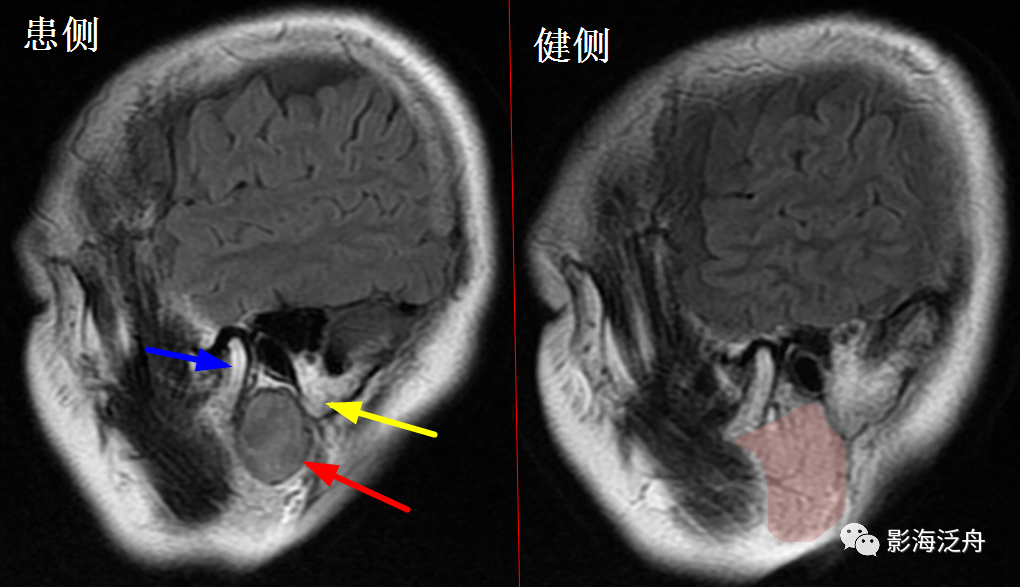

左侧颈内动脉海绵窦段动脉瘤

伴血栓形成(红箭),绿箭为海绵窦段起始端,黄箭头所指为颈内动脉分段的重要解剖标志——前床突(颈内动脉分段可参考之前的文章 颈内动脉CTA分段(超实用))。

海绵窦周围除了动脉瘤外,占位性病变也比较常见,如脑膜瘤、神经鞘瘤、脑外海绵状血管瘤

等。